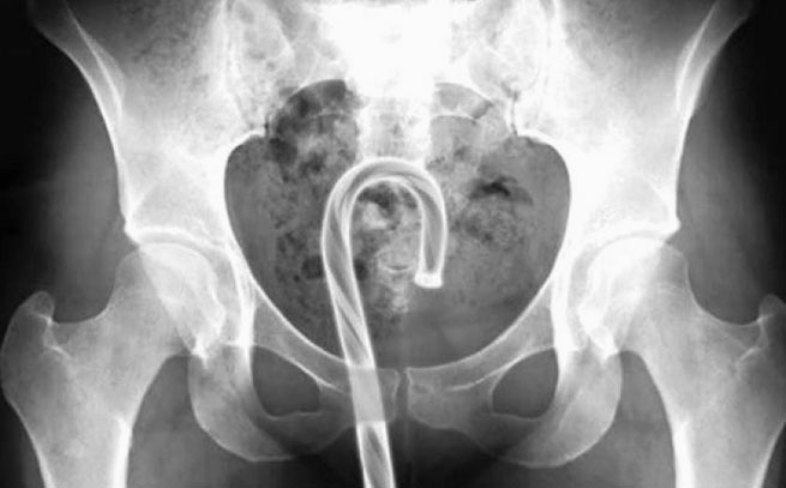

Candy Cane

candy